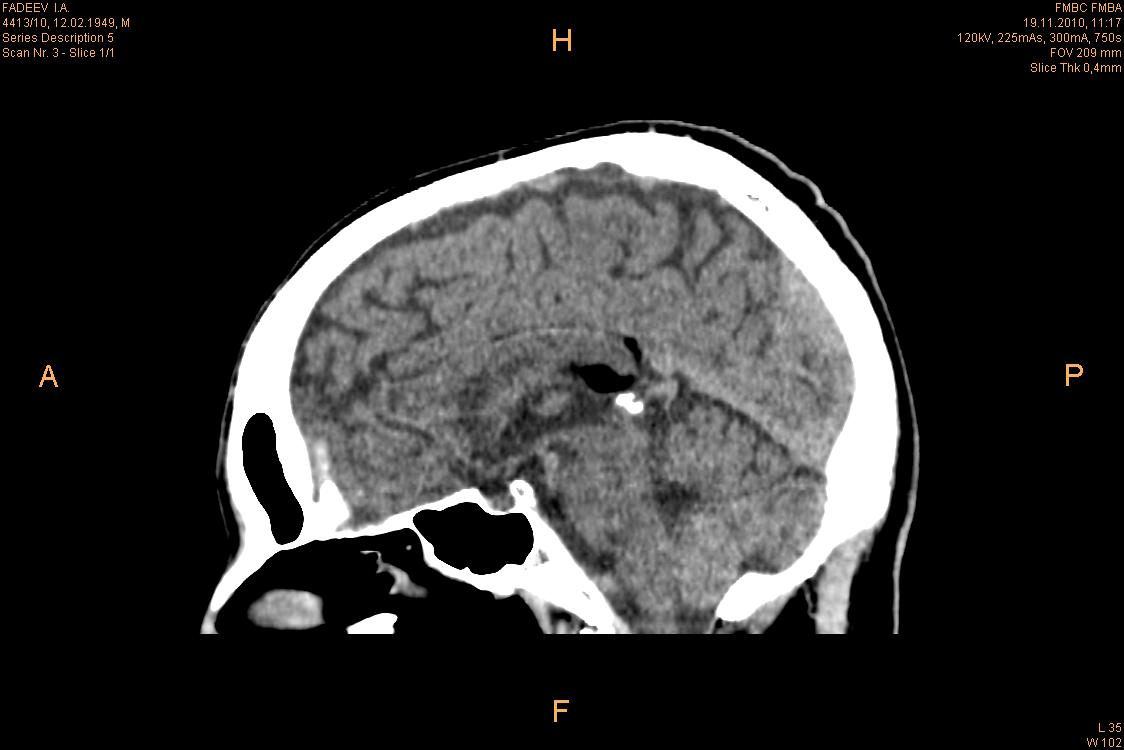

Вот обещал выкладываю!!! Данное образование было расценено, как липома мозолистого тела. Никаких данных зачем и почему делали КТ у меня нет, так как накопал этот случай в архиве, но точно помню, что клиники у пациента никакой не было! возраст 61 год https://radiomed.ru/sites/default/files/styles/case_slider_image/public/user/7335/2.jpg?itok=bIq6Jnnt https://radiomed.ru/sites/default/files/styles/case_slider_image/public/user/7335/3.jpg?itok=X0Zv3ICA https://radiomed.ru/sites/default/files/styles/case_slider_image/public/user/7335/4.jpg?itok=D3AEF2ea https://radiomed.ru/sites/default/files/styles/case_slider_image/public/user/7335/5.jpg?itok=1n7SCA9b ID:52310 Thu, 29/09/2011 - 10:41 #1 Гарик Offline Last seen: 9 years 11 months ago Joined: 21.11.2010 - 19:46 Posts: 16 1Приложения: Игорь Юрьевич Thu, 29/09/2011 - 14:20 #2 Nela Offline Last seen: 6 years 6 months ago Joined: 12.05.2009 - 20:43 Posts: 1847 Ну, да, перикаллезная липома. Случайная находка. Большое спасибо за демонстрацию. Thu, 29/09/2011 - 19:04 #3 Любовь С. Offline Last seen: 9 years 10 months ago Joined: 23.12.2010 - 01:58 Posts: 2324 за демонстрацию. Обратный смайл - за данные о пациенте. "Предоставляя весь смысл и совершенство в распоряжение одного только Бога, вы избавляете себя от бездны хлопот." Джон Уитборн.

Ну, да, перикаллезная липома. Случайная находка.